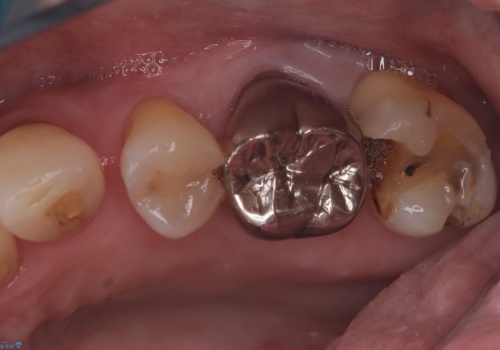

- 主訴:フロスを通したら、詰め物が取れた。適合の良いものを入れたい。

保険適用のメタルインレーが脱離しており、適合重視・咬合力が強いことからゴールドインレーでのやり替えとなりました。

フロスを通しインレーが脱離したことから、インレーと歯質との境に段差(適合不良)があった可能性があり、適合の良さや咬合力による補綴物の破折リスクを考慮し、ゴールドインレーでのやり替えとなりました。